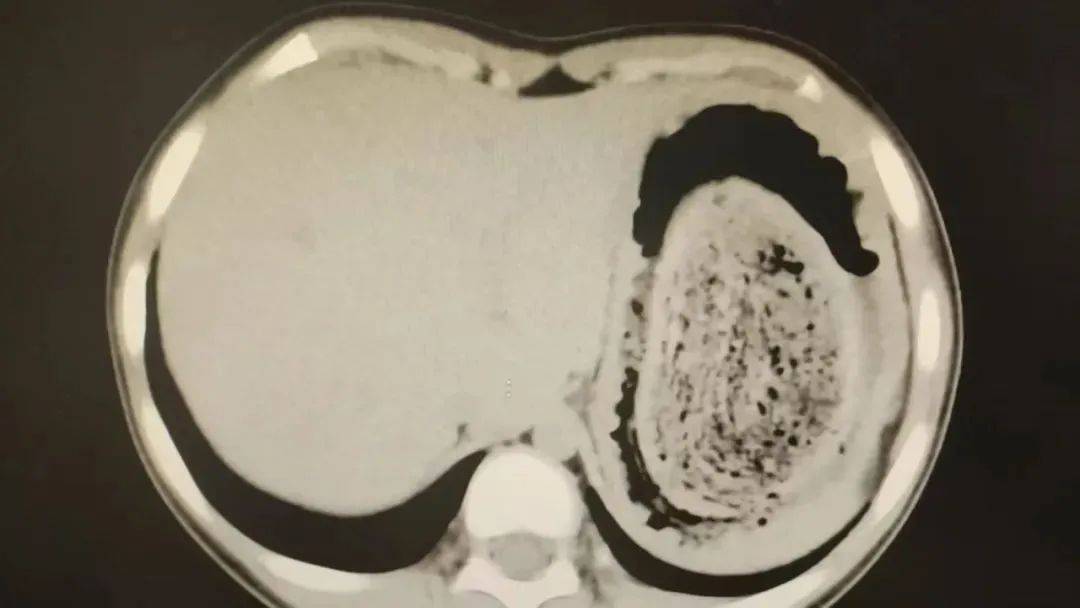

10岁女孩园园(化名)因持续3天的上腹痛伴呕吐被紧急送医皇冠登3管理出租 。影像学检查结果显示,她的胃部存在一个巨大的团块状阴影,初步怀疑为异物堵塞。据家长回忆,园园从1年前开始就有偷偷吃头发的习惯,但家人并未重视,直到这次症状严重才意识到问题的严重性。

在胃镜帮助下,妮妮胃里的情况逐渐明了皇冠登3管理出租 。一个滚圆黑色的毛发球混合着食物残渣占据整个胃腔,这些头发相互缠绕形成一个实心的“发石”,此外胃里还有一个鸡蛋大小的溃疡。

症结找到了,就是这个巨大的发石导致妮妮出现营养不良、贫血和闭经,当务之急就是取出“发石”,给胃进行“大扫除”皇冠登3管理出租 。

“发石”混杂着食物残渣,就像一个黑色的小西瓜皇冠登3管理出租 。由于整个“发石”体积太大,为避免损伤胃壁,医生借助手术工具将“发石”切割、分解,再小心翼翼地分块取出。整场手术持续2个多小时,最终取出4斤头发碎片。